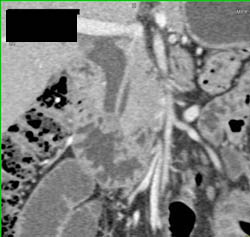

Multiple Intraductal Papillary Mucinous Neoplasms (IPMNs)